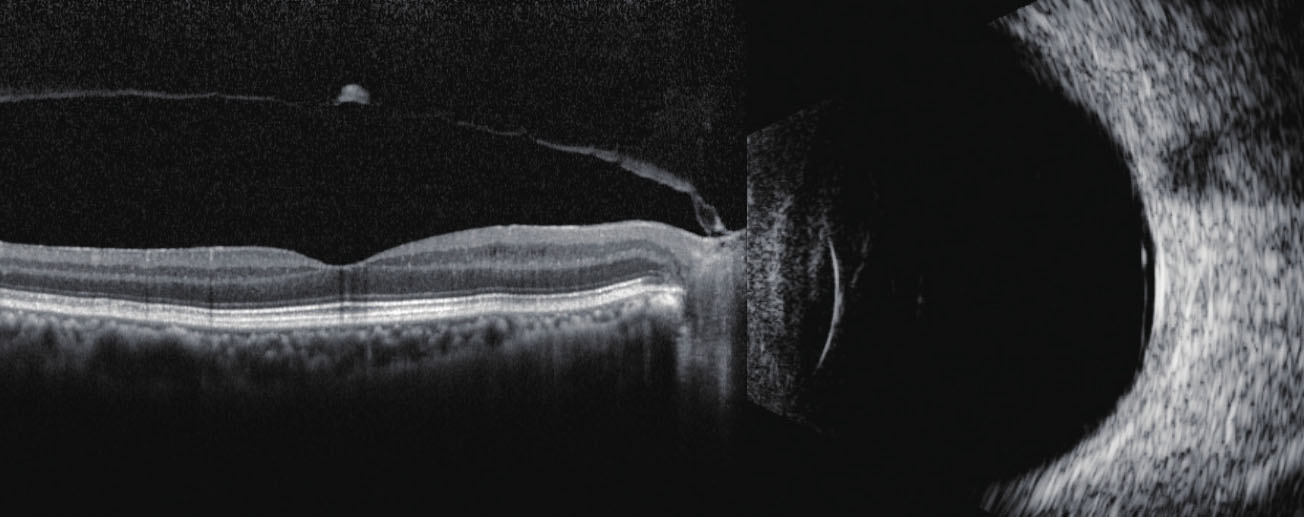

图2—4 不完全性玻璃体后脱离。OCT显示玻璃体后脱离的局部与视盘相连,B型超声显示黄斑区前方有细膜样弱回声,两端分别与视盘及球壁相连